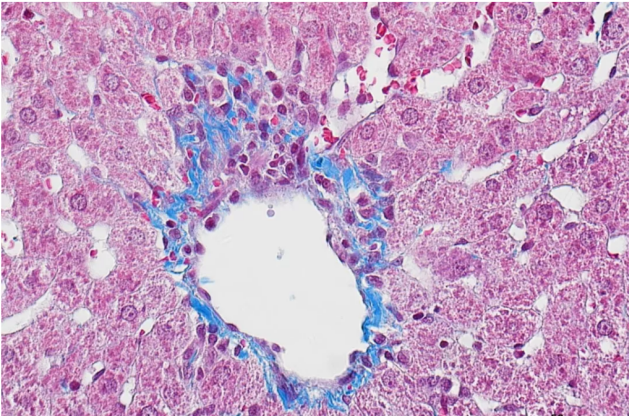

我們上期講過:MASSON染色,作為一種經(jīng)典的結(jié)締組織染色方法,這種方法尤其適用于顯示并區(qū)分膠原、軟骨、黏液、肌纖維等組織成分。普拉特澤生物承接Masson(馬松)染色等病理染色相關(guān)服務(wù)上萬(wàn)例,積累了操作大量經(jīng)驗(yàn),為大家詳細(xì)分享馬松染色的實(shí)驗(yàn)操作步驟與染色結(jié)果分析,同時(shí)為廣大科研工作者開展線上的理論培訓(xùn)與線下實(shí)操,可承接染色實(shí)驗(yàn)外包服務(wù)~下面將詳細(xì)介紹MASSON染色的專業(yè)步驟及相關(guān)技巧。

·無(wú)需水洗,直接使用苯胺藍(lán)或光綠液進(jìn)行反染,使膠原纖維、粘液、軟骨等組織成分呈藍(lán)色或綠色。